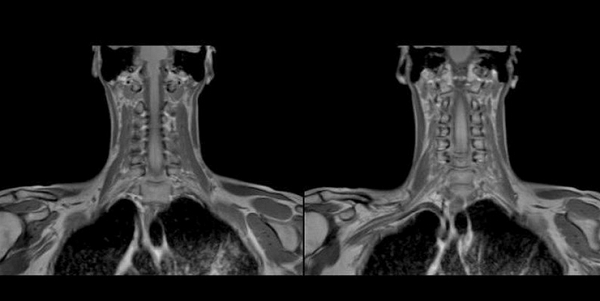

Результаты МРТ

T1WI: Изоинтенсивное расширение орбит

T2WI: острый сигнал от жировой ткани (отек); поздняя стадия: снижение сигнала (фиброз)

T1 с контрастом: улучшение изображения орбитального жира, который более выражен чем норма

Снимки МРТ мягких тканей шеи

Магнитно-резонансная томография обеспечивает детальную визуализацию рыхлых структур. В результате сканирования получают послойные изображения щитовидной железы, расположенных рядом лимфатических узлов, кровеносных сосудов, мягких тканей шеи, гортани.

Исследование отличается высокой информативностью по сравнению с другими методами аппаратной диагностики. Томограммы показывают изменения формы и размеров анатомического образования, позволяют выявить структурные нарушения и патологические очаги диаметром от 3 мм.

При увеличении железы в размерах по описанию томограмм можно определить характер гиперплазии. Узелки и капсулы выглядят на снимках МРТ как очаги с гипо- или гиперинтенсивным сигналом, отличным от реакции окружающих тканей. Метод показывает сдавление трахеи новообразованием, распространение патологического процесса в загрудинное пространство.

Мягкие ткани шеи на МРТ